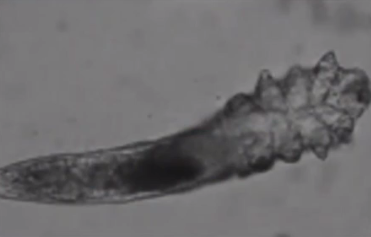

关爱眼健康不仅要提倡少看电子产品,还要注意眼部卫生,否则容易在眼周滋生一种寄生虫,即:蠕形螨,简称螨虫。

螨虫喜欢吃油的东西。在眼睛周围,最适合螨虫生长的部位是睫毛毛囊和睑板腺开口,两处均是油脂分泌旺盛的地方。当携带各种病菌的螨虫大量聚集时,容易引起炎症反应,导致睑缘充血,形成反复发作的眼痒、眼红、畏光、异物感及烧灼感等睑缘炎及干眼症状,同时还可能会分泌白色鳞屑状分泌物。